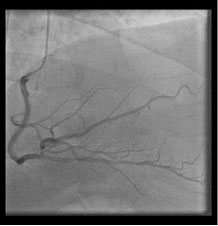

Figure 1: (Labeled and unlabeled).

The left main coronary artery (star) is elongated and gives rise to the left anterior descending artery and a substantial diagonal artery (arrow), but there is no left circumflex artery visible in this right anterior oblique, caudal view via cinematography during the left heart catheterization. View Figure 1